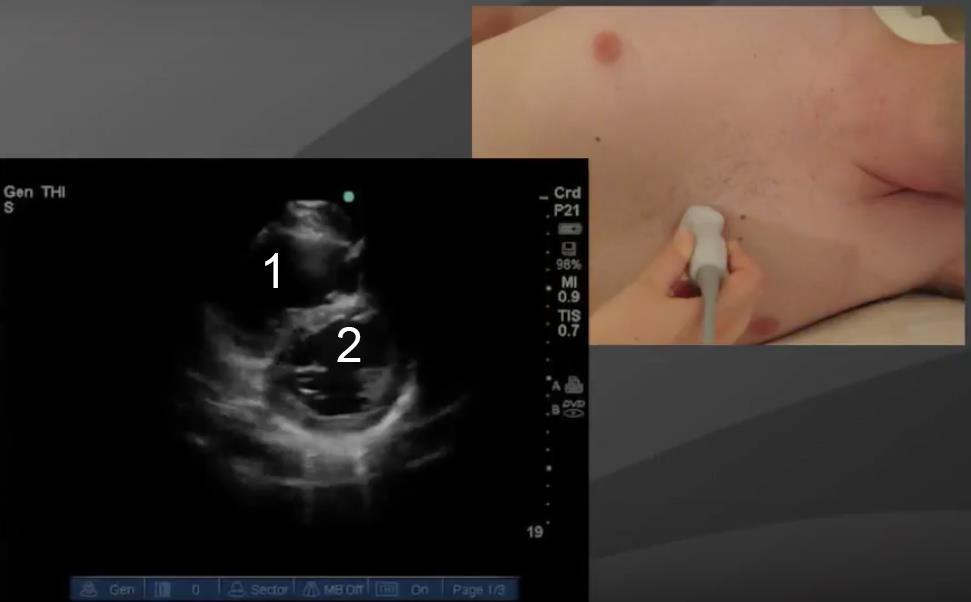

Cardíaco: Vista paraesternal del eje transversal 2 - Imagen

1. Ventrículo derecho (VD)

2. Ventrículo izquierdo (VI)